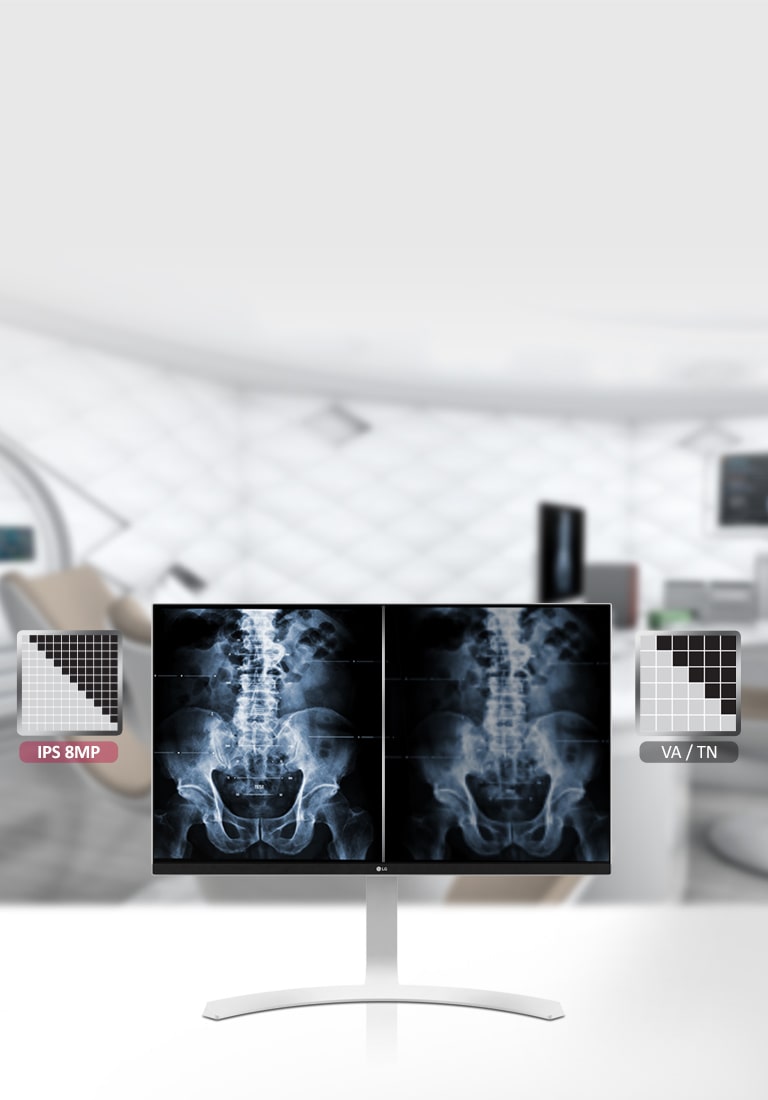

27" 4K & 5K UHD Màn hình y tế

Độ phân giải

3840 x 2160

Tỷ lệ tương phản (Typ.)

1000:1